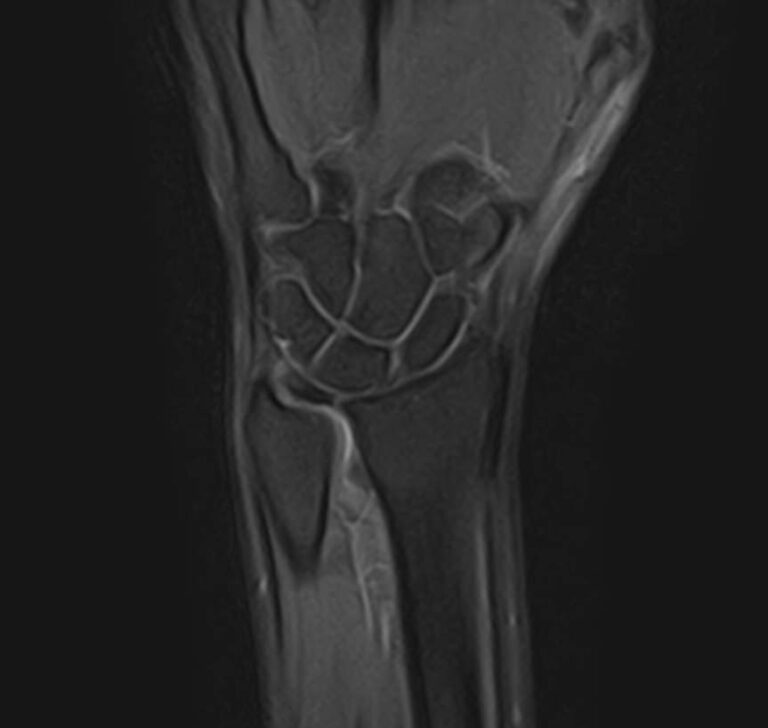

МРТ является современным высокоинформативным неинвазивным и при этом безопасным методом исследования, который позволяет детально визуализировать состояние всех структур лучезапястного сустава, включая дистальные отделы лучевой и локтевой костей, хрящей, сухожилий, нервов и окружающих мягких тканей.

В клинике «Доступная медицина» исследование проводится на новейшем высокопольном томографе экспертного класса TOSHIBA VANTAGE TITAN 1,5 Тесла, который делает послойное сканирование исследуемой области в различных плоскостях с шагом от 1 мм и в дальнейшем преобразует полученные данные в трехмерные изображения. Результаты МРТ позволяют выявлять заболевания лучезапястного сустава на начальных стадиях и назначать своевременное лечение.